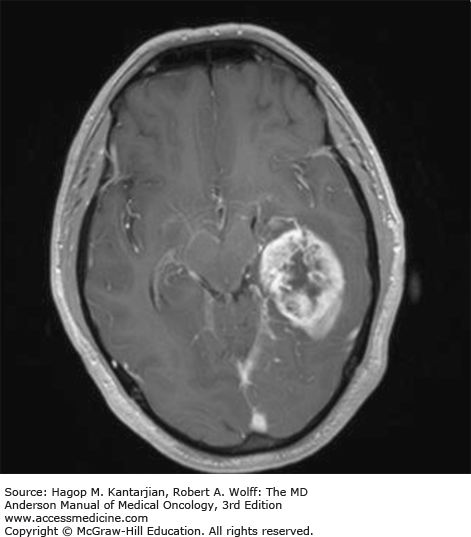

Glioblastoma